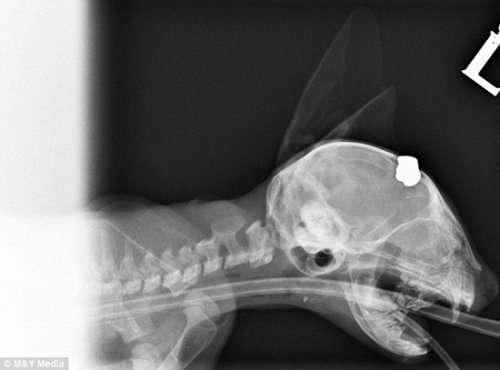

- 英国6周大小猫头部连中两枪 经救治奇迹生还(组图)

- 时间:2012-08-06 11:21:42